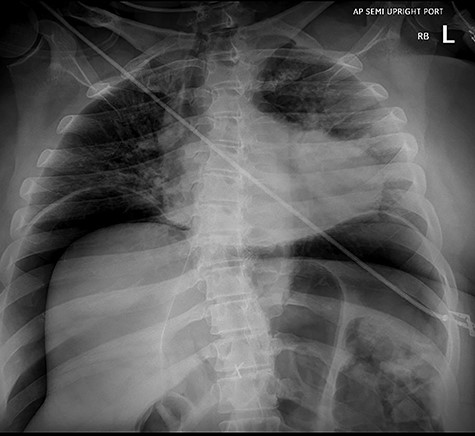

Abdominal exploration was started laparoscopically. Upon incising the midline fascia a large amount of air came out under pressure. The patient abruptly became hypoxic, hypotensive and the previously normal end tidal CO2 was noted to have increased to 90 mmHg, despite the fact that abdominal insufflation with CO2 had not yet started. At this time, a midline incision was made to explore the abdomen. Diffuse bowel ischemia and distension of both the small and large intestines were observed. A 1-cm perforation with dark sanguineous output was noted at the jejuno-jejunal anastomosis staple line. A large amount of intraluminal blood was suctioned through the perforation. A segmental small bowel resection containing the anastomosis was performed (Fig. 4). Intraoperative blood testing revealed a hematocrit of 23%, lactate 7.8 mmol/l, potassium 8.0 mEq/l and blood glucose 3.0 mg/dl.

Resected specimen of jejuno-jejunal anastomosis with perforation.